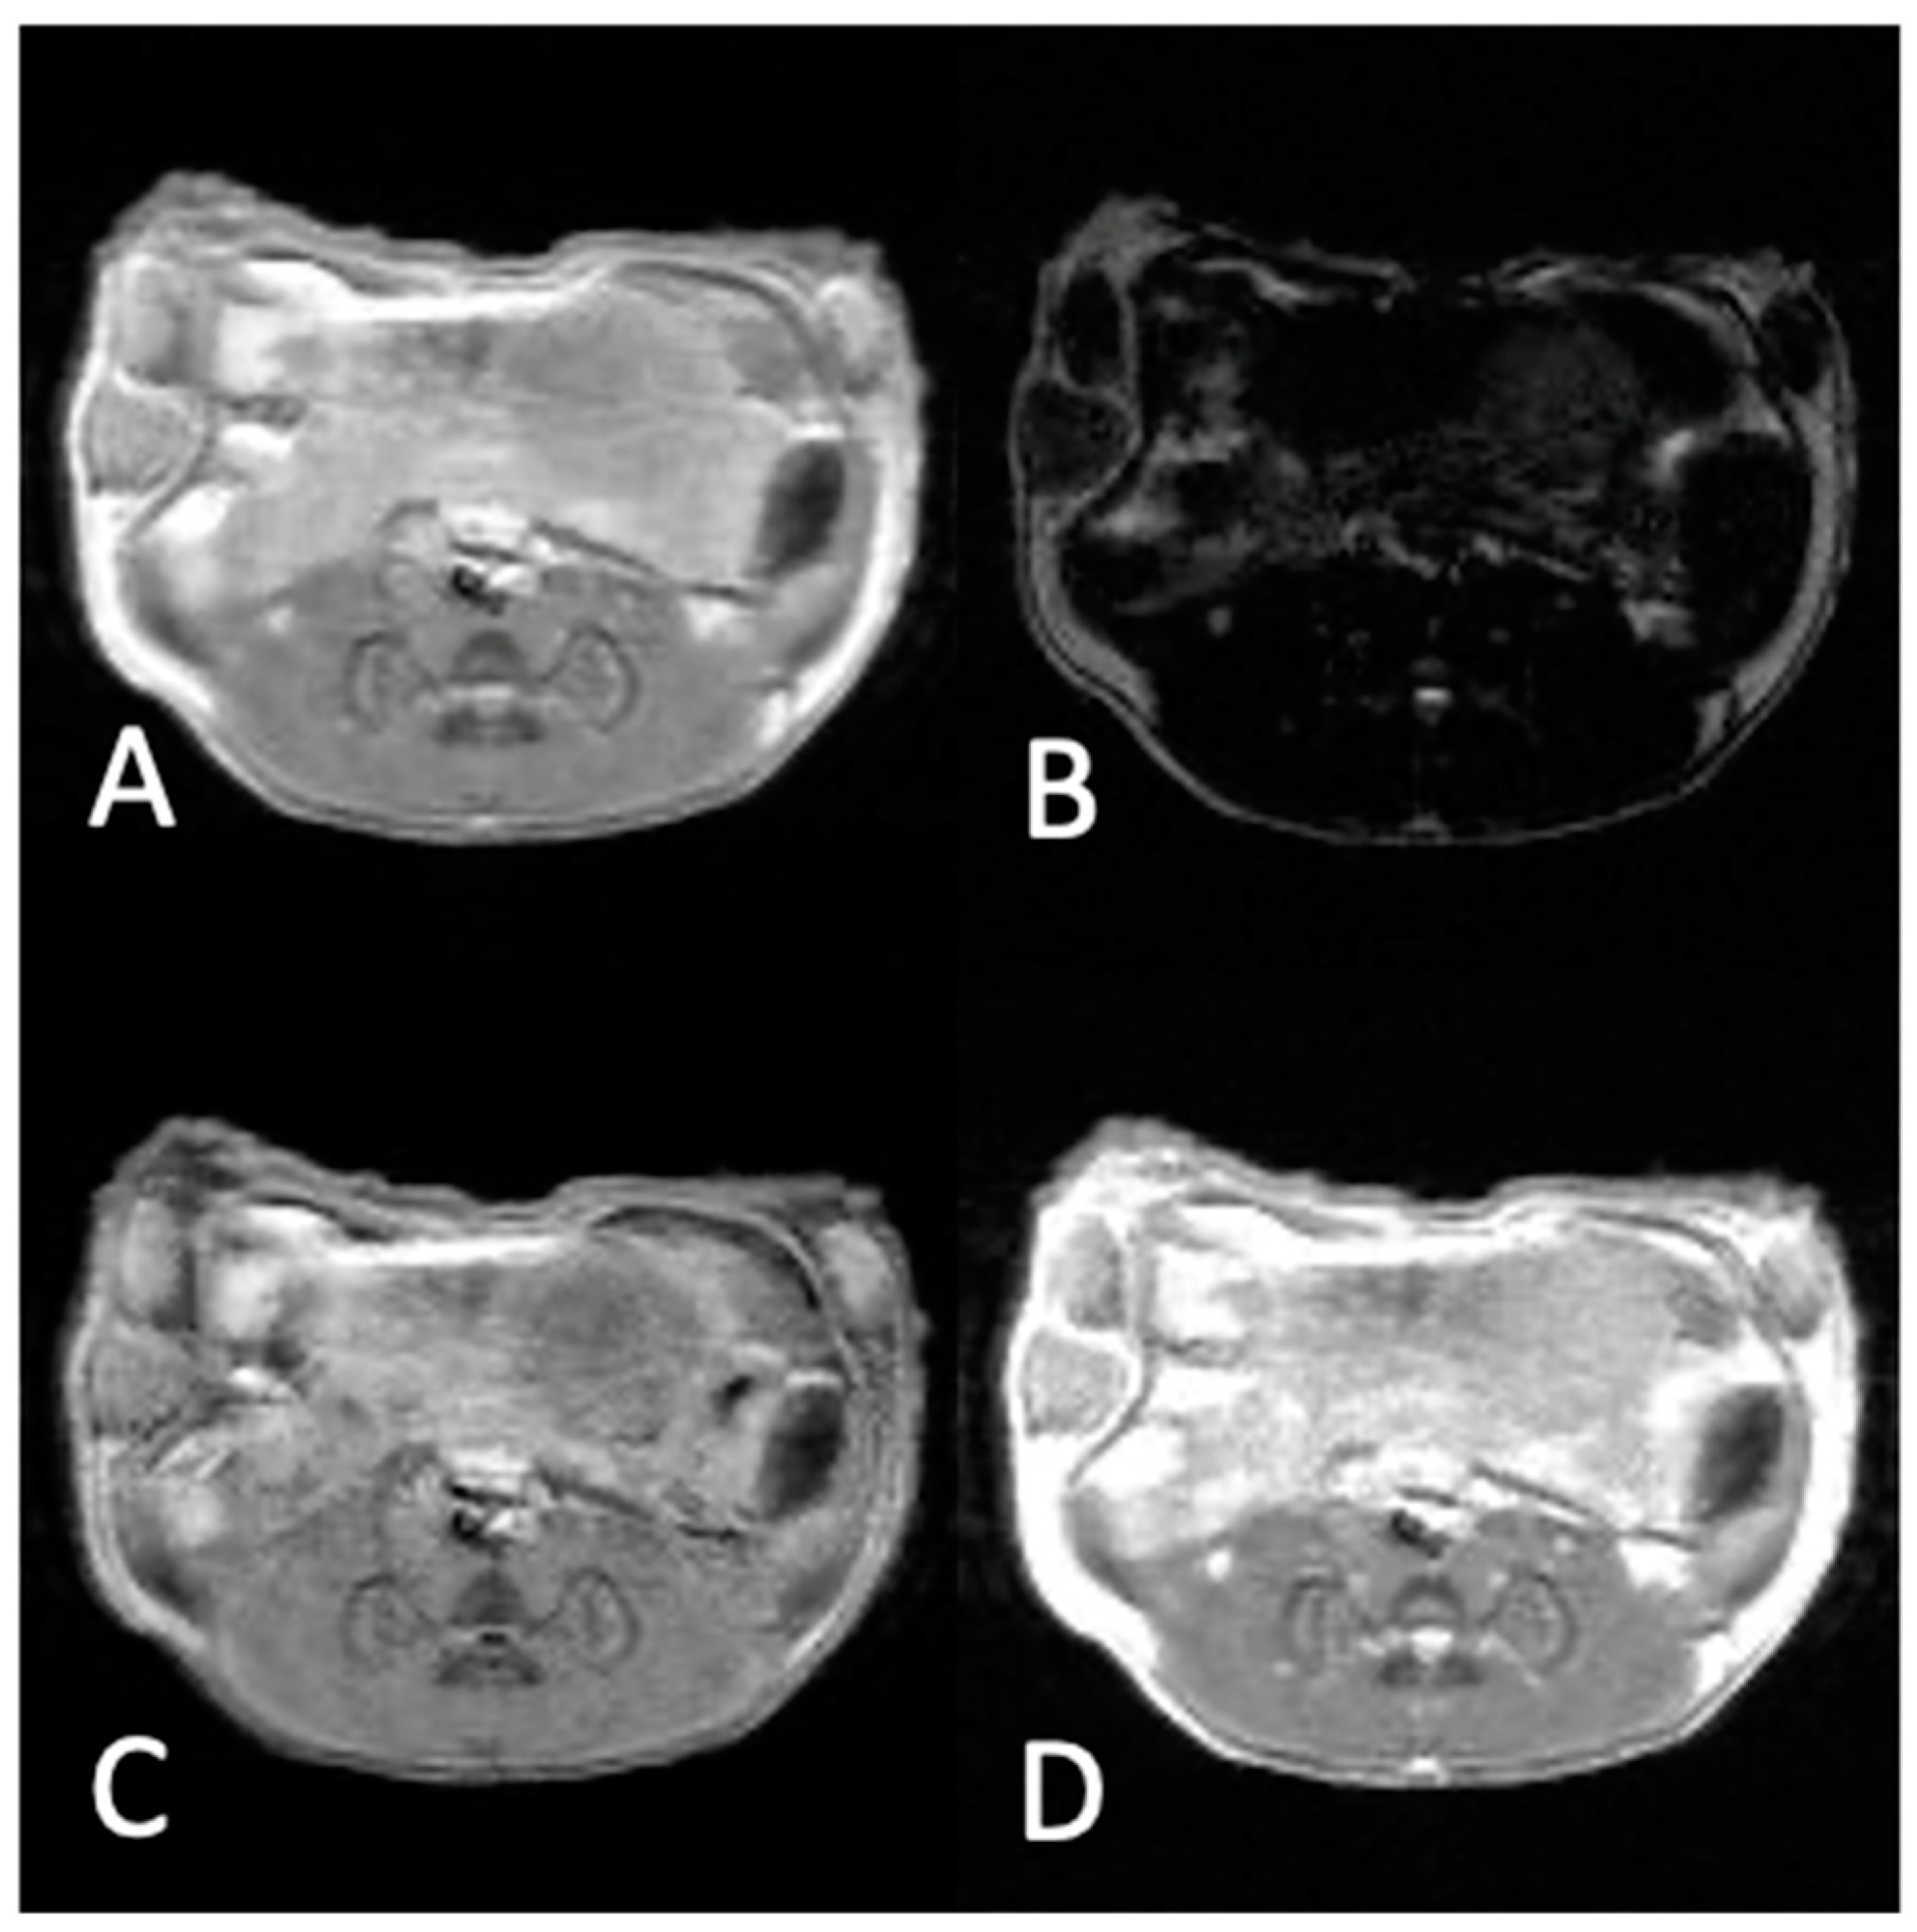

2.4. In Vivo MRI Experiments

2.5. MR Imaging Parameters

3.2. In Vivo Experiments